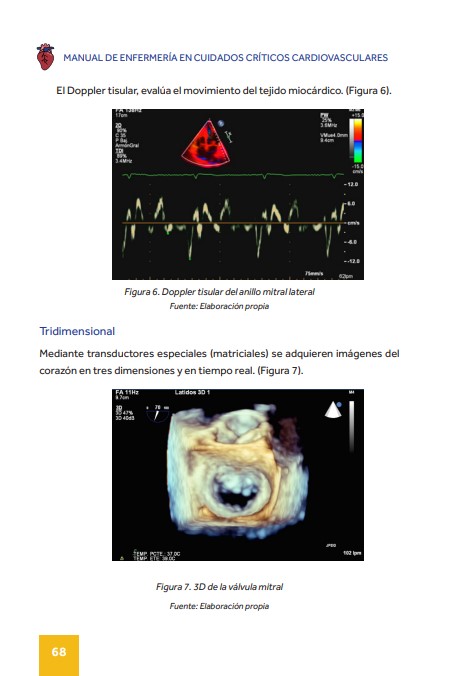

Dentro del manual podemos encontrar apartados interesantes como la Ecocardiografia, con numerosas imágenes y esquemas.